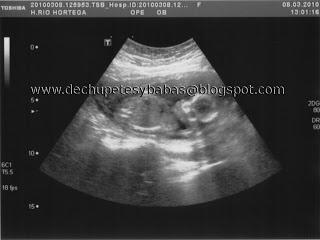

A la semana de la prueba, tenía cita con el ginecólogo para hacerme una ecografía y ver cómo estaba todo. Vio que estaba todo bien y allí vi muy clarito a mi garbancito:

Como estaba claro que mi embarazo no podía ser tranquilo, en esa ecografía el ginecólogo me detectó una brida amniótica. Me dijo que si iba a buscar en internet, iba a ver que esas bridas podían causar deformidades en el feto, pero que no me preocupara porque en mi caso la brida había salido tarde, mi niña estaba ya formada. Ay, Dios, creí que me daba algo, ¿cómo no me iba a preocupar? Le pregunté si la dichosa brida podía haber salido por la amnio y me dijo que era probable. Tenía ya tantas cosas de qué preocuparme, que de alguna manera deseché la angustia por la brida, pero sí lo pensaba de vez en cuando. Y ahí estuvo la brida el resto de mi embarazo. Por suerte, no afectó a mi niña.